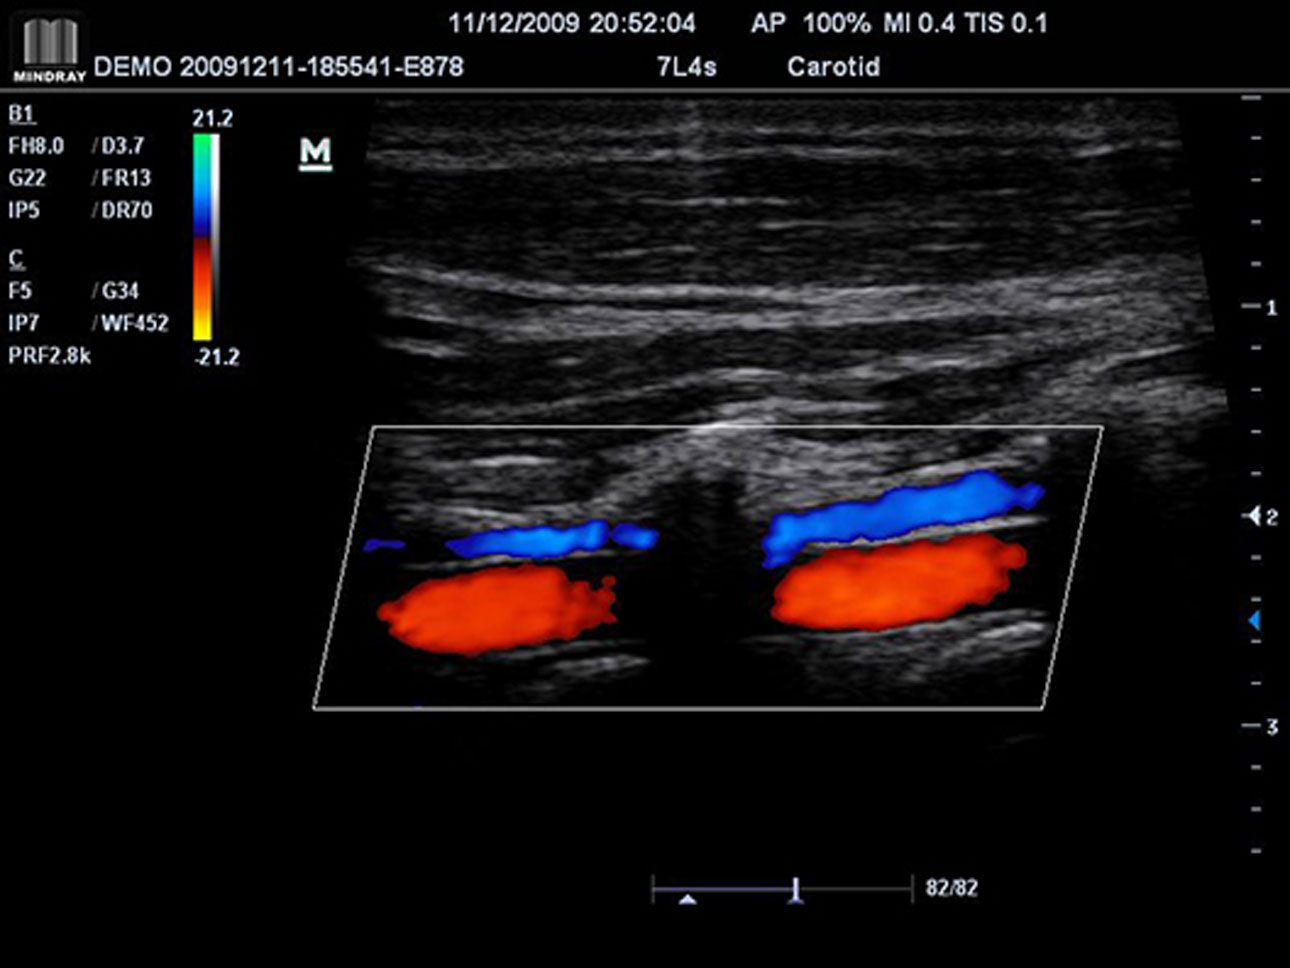

IMT (Intima-Media Thickness)

Auto measurement of anterior and posterior wall thickness providing accurate carotid status.